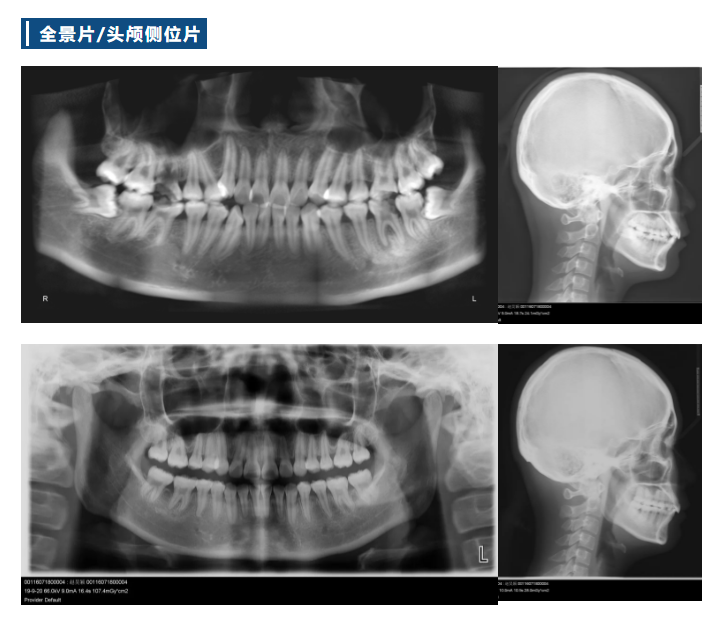

Z2 病例分享 | 一例减数上下颌四颗第一磨牙矫治拥挤病例(雷蕾)